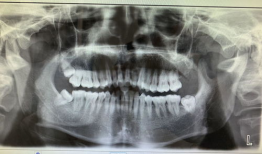

你知道吗?拔智齿这个话题,最近在网络上可是火得一塌糊涂呢!很多人都在好奇,拔智齿到底是个啥样的过程,是不是像传说中的那么恐怖?今...